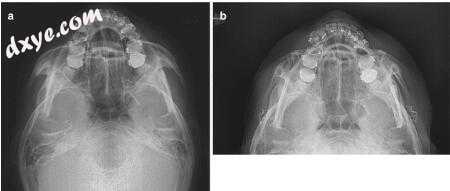

在切骨的颧骨向内侧(5mm)和向后(2mm)移位后,用微型板和螺钉固定。颧骨的身体用双桥板固定,以提供抵抗来自咬肌的扭矩的稳定性(图16.7a)。颧骨弓用预弯板固定,以获得准确的位置和稳定性(图16.7b)。术后6个月,颧骨突出和中间面宽度明显减少(图16.8)。

图16.7病例1.(a)术前和(b)术后放射照相显示颧骨后内侧重新定位